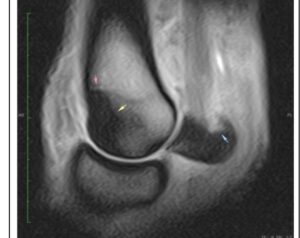

Signs: Bone edema or bone bruising are painful, so your horse will be sore. Your vet can isolate the painful area with nerve blocks, but sophisticated imaging techniques may be necessary to identify the cause. X-rays will not show microscopic bone damage, but a edema/hematoma may appear as a “hot spot” on a nuclear bone scan. MRI is a good diagnostic technology to outline the edema/hematoma.

MRI-Bone Edema